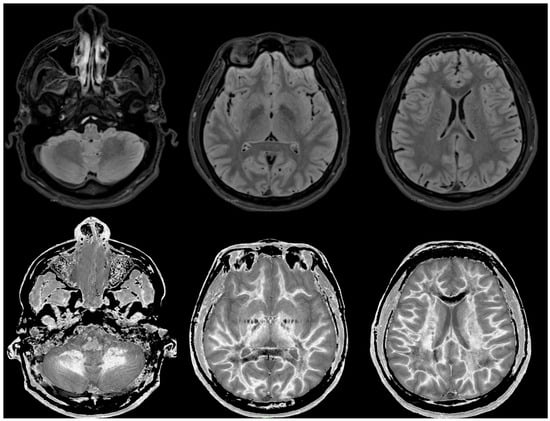

Figure 4 and Figure 5 show T2-FLAIR images (upper rows) with positionally matched dSIR images (lower rows). No abnormality is seen in white matter on the T2-FLAIR images, but very extensive high signal abnormalities are seen in white matter on the corresponding dSIR images. In Figure 4, there is sparing of white matter in the anterior central corpus callosum and adjacent forceps minor, which have a dark appearance (long white arrows). There is also some sparing of the posterior central corpus callosum. In Figure 5, there is sparing of the peripheral white matter of the cerebral hemispheres, which have a dark appearance (long white arrows). Small focal lesions of a relatively increased signal are also seen in the white matter in Figure 5 (grey arrows) on the dSIR images. High signal boundaries between the white and grey matter are seen, but these are less obvious in many areas because of the high signal present in much of the white matter.

Overall, the abnormalities are bilateral and symmetrical and involve most of the white matter of both the cerebral and cerebellar hemispheres. The appearances in the patient are strikingly different from those in the normal control shown in Figure 3, where normal white matter has a low signal (dark appearance), apart from the corticospinal tracts and areas adjacent to them, which are mid-grey.

Figure 4. Case 1 was examined nine months after a severe drug overdose. Comparison of positionally matched T2-FLAIR images (upper row) and narrow mD dSIR images (lower row). No abnormality is seen on the T2-FLAIR image, but there are extensive areas of a high signal in the white matter of the brain. Only the anterior and posterior central corpus callosum and parts of the frontal lobes have a low signal (dark appearance) and look normal on the dSIR images (white arrows) (lower row). High signal boundaries are seen at the junction between the white matter and grey matter but are rendered less obvious in many areas because of the high signal in much of the white matter.

Figure 5. Case 1 was examined nine months after a severe drug overdose. Comparison of positionally matched T2-FLAIR images (upper row) and narrow mD dSIR images (lower row) (higher cerebral hemispheres). No abnormality is seen on the T2-FLAIR images, but there are extensive areas of high signals in the central white matter of the brain (lower row). Only some of the peripheral white matter on the lower images appears dark and looks normal on the dSIR images (white arrows) (lower row). Some other areas of white matter have a mid-grey appearance consistent with a lesser degree of abnormality. Small focal lesions are also seen on the dSIR images (grey arrows) but not on the T2-FLAIR images.